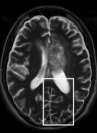

While the scenario of longitudinal studies is fundamentally different from dynamic MRI in many aspects, we still find that similarity across time points exists in many cases. Figure 1 shows an example of the same axial slice taken from multiple scans acquired from a patient with Optic Pathway Glioma (OPG), demonstrating a relatively slow growing tumor pattern. The bottom row of the figure shows the representation of each time point in Daubechies-4 wavelet transform (Daubechies et al., 1992), which is widely used as a sparse transform for brain MRI. The similarity between image slices acquired at several time points is clearly demonstrated. Moreover, the representation of the images in the wavelet domain is sparse, and the locations of the dominant wavelet coefficients (a.k.a the support of the image in the wavelet domain) are similar across the patient’s time points.

Note that term 2 is sparse if there are no major changes between and , both images have similar grey-level intensities and they are spatially matched. While these conditions meet in many application of dynamic imaging, such as prior image constrained compressed sensing (PICCS) in CT (Chen et al., 2008; Lauzier et al., 2012) and dynamic MRI (Jung et al., 2009; Lustig et al., 2006; Gamper et al., 2008; Yip et al., 2014), in longitudinal MRI none of these requirements are guaranteed. While there are solutions for miss-registration and variable grey level intensities (see Section 4), the temporal similarity in longitudinal MRI is a-priori unknown. Although longitudinal MRI may exhibit temporal similarity (Samsonov et al., 2010), we have to take into account that in many cases the follow-up scan may exhibit substantial changes with respect to the baseline scan. Such cases may occur, for example, if a surgical intervention was applied between the time points or if there is a major progressive or therapy response. Figure 2 shows two representative examples.

Baseline 4 months Baseline 3 months

Hydrocephalus GBM